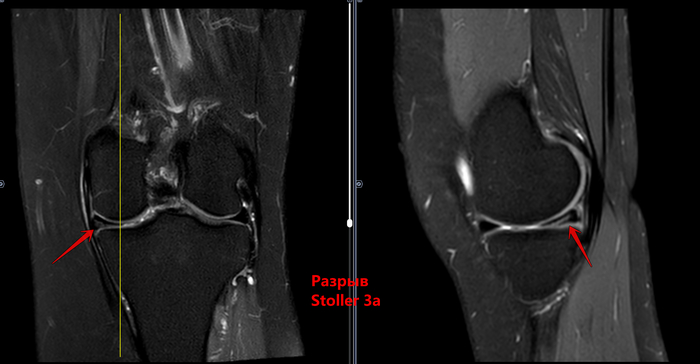

МРТ-Повреждение мениска коленного сустава Stoller 3a⁠⁠

6 месяцев назад

Описание: В структуре внутреннего мениска левого коленного сустава определяется линейный продольный косогоризонтальный патологический МР-сигнал от повреждения с распространением на дистальную суставную поверхность в области тела, заднего рога (соответствует IIIа ст. по Stoller). В области заднего рога медиального мениска определяется многокамерная киста, размерами 1,6х0,7х1,5 см.Целостность крестообразых связок сохранена.В области энтезиса сухожилия медиальной головки икроножной мышцы определяется утолщение, разволокнение.В области сухожилия полуперепончатой мышцы определяется многокамерное жидкостное образование неправильной формы, размерами 1,0х2,8х4,0 см (киста Бейкера).Краевых остеофитов нет.Интенсивность сигнала от клетчатки Гоффа без особенностей. Убедительных данных за патологические изменения остальных видимых мягких тканей не получено.

Заключение:

МР картина повреждения внутреннего мениска (IIIа по Stoller) левого коленного сустава; интерстициальное повреждение внутренней коллатеральной связки; энтезопатии сухожилия медиальной головки икроножной мышцы. Умеренный синовит, супрапателлярный бурсит. Киста заднего рога медиального мениска. Киста Бейкера.